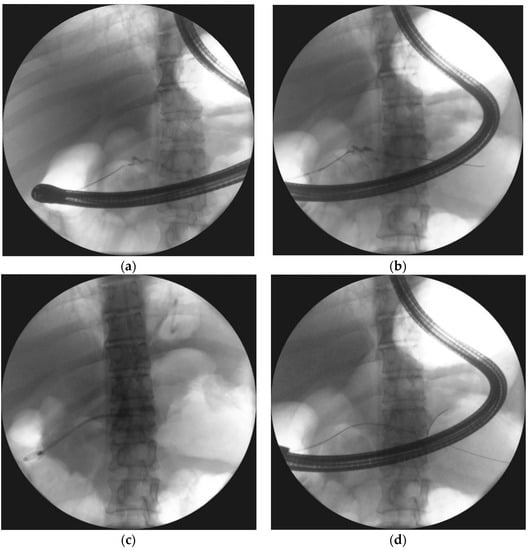

- Smoczyński, M.; Jagielski, M.; Jabłońska, A.; Adrych, K. Endoscopic necrosectomy under fluoroscopic guidance- a single center experience. Wideochir. Inne. Tech. Maloinwazyjne. 2015, 10, 237–243. [Google Scholar] [CrossRef] [PubMed]

| Endoscopic necrosectomy under fluoroscopic guidance (endoscopic debridement) | Procedure that enable to remove necrotic tissues from necrotic cavity through transmural fistula under fluoroscopy with use of various types of endoscopic tools. Indication for endoscopic debridement is WOPN containing poorly-liquefied necrotic tissues. |